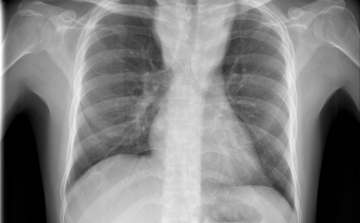

Menekültek révén, egy líbiai táborból érkezhetett Európába a tuberkulózis (tbc) kórokozójának egy korábban ismeretlen, gyógyszerekkel szemben ellenálló fajtája - írta a Die Welt című német lap a hírportálján szerdán.

Hétfő reggel óta tbc-tesztet végeznek el a gyerekeken egy szatymazi általános iskolában, ahol egy hete fertőző tüdőbetegségben halt meg egy korábban ott dolgozó nő - közölték az M1 aktuális csatorna déli Híradójában.

Átlagosan 4,3 százalékkal csökkent az új tuberkulózisos (tbc-s) esetek száma 2010 és 2014 között az Egészségügyi Világszervezet (WHO) 53 országot magába foglaló európai régiójában.

A tuberkulózis, a kanyaró, a HIV és a rezisztens baktériumok terjedése aggodalomra adhat okot Európában – állapították meg a régió járványügyi szervezetének (ECDC) éves jelentésében.

40 millió dohányos halhat meg tbc-ben 2050-ig

A kutatók szerint akár a 40 milliót is elérheti azoknak a dohányosoknak a száma, akik 2050-ig tuberkulózisban (tbc) veszítik életüket.